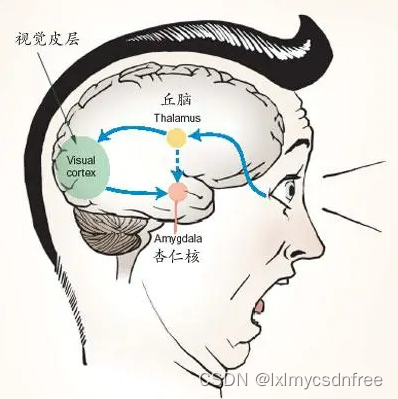

(上图:外界的情绪刺激到达的首位置就是杏仁体)

刺激清醒动物的杏仁核,动物出现“停顿反应”,显得“高度注意”,表现迷惑、焦虑、恐惧、退缩反应或发怒、攻击反应。刺激杏仁首端引起逃避和恐惧,刺激杏仁尾端引起防御和攻击反应。诱发惧—怒反应时伴瞳孔扩大、竖毛、嗥叫等情绪表现。切除杏仁核,动物出现“心理性失明”:通过视觉看到的东西不知是否可以吃,必需放到嘴里才知道;“过度变态”:反复察看、触摸或以口检查各种物体,包括原先所畏惧的活蛇或活鼠;情感性行为发生显著变化或所有的情感反应完全丧失。关于情绪反应的产生机制,有人研究认为存在两条反射通路。(1)刺激—〉丘脑—〉扣带回—〉大脑各区域相应皮质(长通路);(2)刺激—〉丘脑—〉杏仁核(短通路)。长通路的刺激信息经过皮质的精细加工,利于对情绪的控制和采取适当的应对方式,短通路的刺激信息未经皮质的精细加工,速度更快,保证对恐惧刺激作出迅速反应,这对包括人在内的所有生物的生存十分重要。由此可见,杏仁核的主要功能为产生和传入大脑新皮质的各种外界信息相适应的情绪。